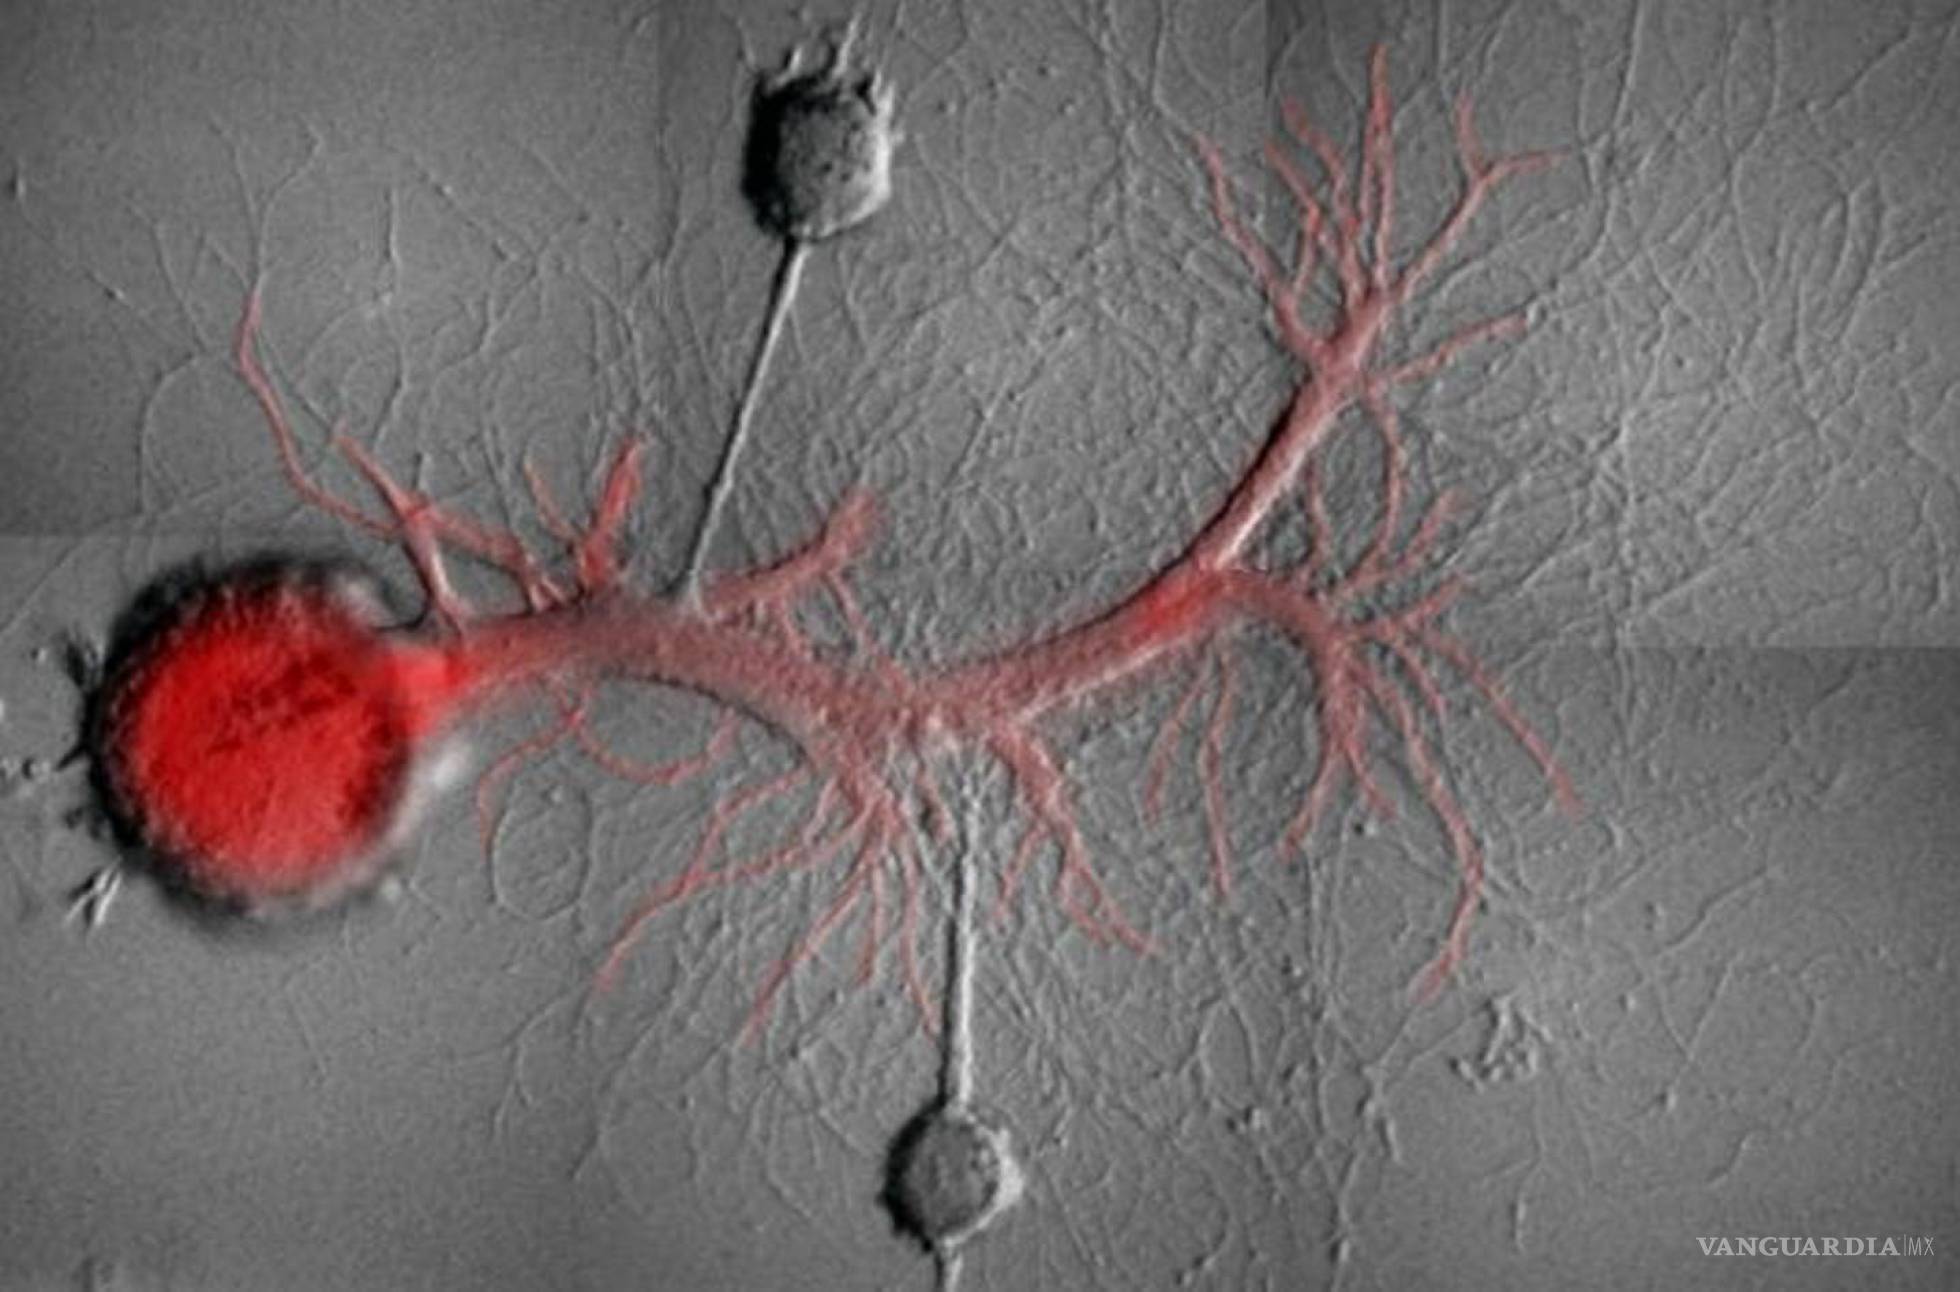

Para esto, los investigadores emplearon babosas marina del género aplysia quienes tiene  grandes neuronas en las que se puede observar con facilidad la memoria en acción.

Ante esta hipótesis, los autores del estudio estimularon a dos neuronas sensoriales conectadas a una neurona motora. Una de las neuronas se estimuló para inducir una memoria asociativa y la otra no asociativa.

Analizando la fuerza de dichas conexiones, descubrieron que los distintos tipos de memoria asociadas a distintos estímulos se mantenían gracias a dos variantes de una proteína. Por tanto, los científicos lograron borrar un tipo de memoria son afectar a la otra bloqueando la proteína adecuada.